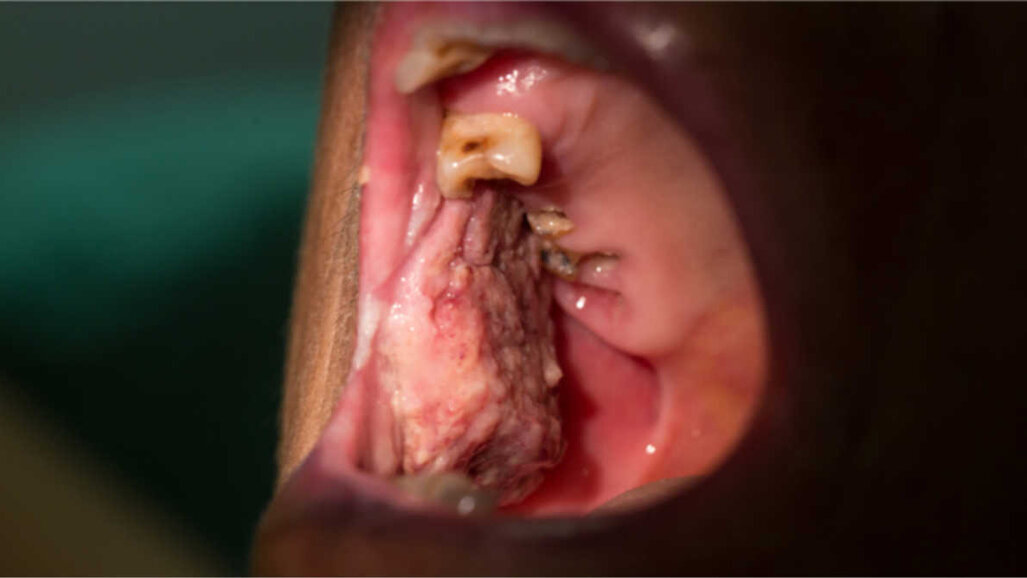

Podczas lockdown Stassen zidentyfikował 2 przypadki raka jamy ustnej na podstawie zdjęć przesłanych mu przez pacjentów, jednak wielu z nich nie rozpoznaje lub nie reaguje na objawy nowotworowe, ponieważ obawiają się możliwego zakażenia SARS-CoV-2 albo nie wie, że w okresie powszechnego zamykania gabinetów dentystycznych nadal działają pogotowia dentystyczne. Jak zauważył Stassen, przed pandemią dentyści diagnozowali 150-180 przypadków raka jamy ustnej, głowy i szyi rocznie.

Przypadki nowotworów w zakresie jamy ustnej wykryte we wczesnym stadium dają wskaźnik przeżycia na poziomie ok. 90% i mogą wymagać jedynie niezbyt rozległych zabiegów chirurgicznych. Przypadki wykryte na późniejszym etapie rozwoju mają obniżony wskaźnik przeżycia wynoszący tylko 5-10%. Kontrole są ważne nie tylko dla pacjentów, u których wystąpiły objawy podczas pandemii, ale także dla tych, którzy wyzdrowiali, aby upewnić się, że choroba nie powraca.

Stassen powiedział też, że w ostatnich 10-15 latach leczenie nowotworów jamy ustnej znacznie się poprawiło, ale dodał, że na wielu płaszczyznach COVID-19 zniszczył te osiągnięcia.